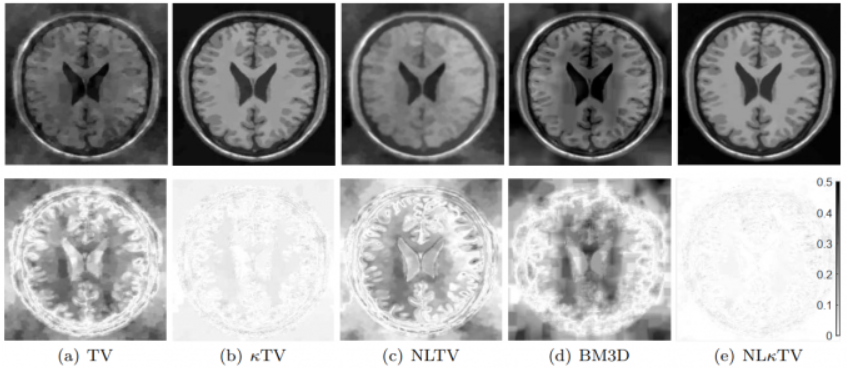

课题组提出了非局部的曲率正则化方法, 并应用于CS-MRI重建问题。如图所示, 在10%采样率的情况下, 我们的结果明显好于SOTA, 相关结果发表于Journal of Mathematical Imaging and Vision。